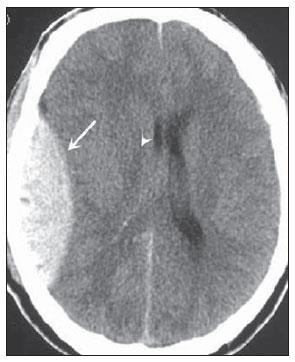

Observe a imagem tomográfica abaixo, analise os excertos e assinale a alternativa correta:

Enunciado 2968768-1

http://www.rb.org.br/detalhe_artigo.asp?id=2613&idioma=Portugues

I – Tomografia Computadorizada com AVCI do território da Artéria Cerebral Posterior (ACP).

II – A;B - Infarto parcial, com envolvimento restrito ao hemisfério esquerdo.

III – C;D: Infarto completo à esquerda, com efeito de massa comprimindo o ventrículo lateral.

IV - No hemisfério direito visualiza-se hipodensidade esquerda maior.

Está correto o que se afirma em: